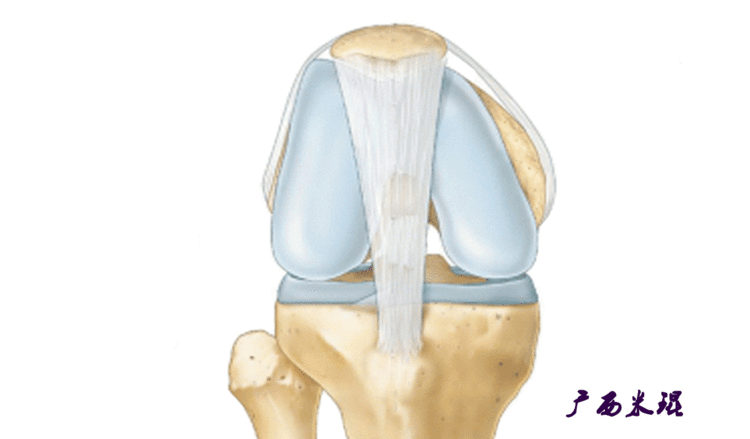

从0到30°限制髌骨外侧位移最重要的是MPFL(内侧髌股韧带),文献报道认为导致髌股关节不稳的主要原因是内侧髌股韧带损伤,而在限制髌骨向外移位过程中,内侧髌股韧带提供约60%的力量,所以重建MPFL是治疗复发性髌骨脱位的有效方法。即使这样,MPFL重建也不是万能的,寄希望于MPFL重建解决所有的髌骨脱位肯定是不现实的,MPFL重建有着严格的适应症和技术要求,对于骨骺未闭合者,股骨端的骨隧道必须避开骺板,以免影响骨骼的生长。